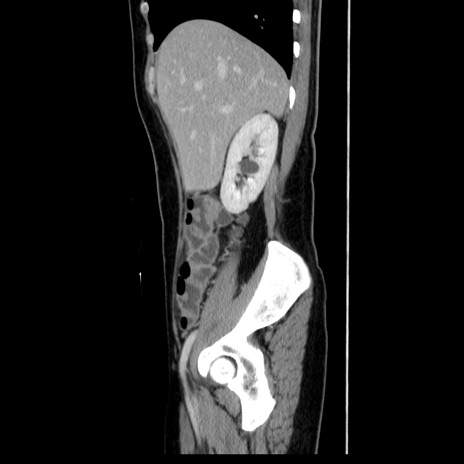

症例39(矢状断像)

【症例】40歳代女性

【主訴】上下腹部痛

【現病歴】2日目から下腹部痛あり。夜間は痛みで眠れなかった。昨日より上腹部痛と下痢が出現。臥位で痛みは軽快したため、休んでいた。本日になって臥位でも立位でも痛みが強くなってきたため救急要請。

【既往歴】子宮内膜症

【身体所見】部:平坦・軟、左上下腹部に圧痛あり、反跳痛あり。

【データ】WBC 21800、CRP 26.78

CT